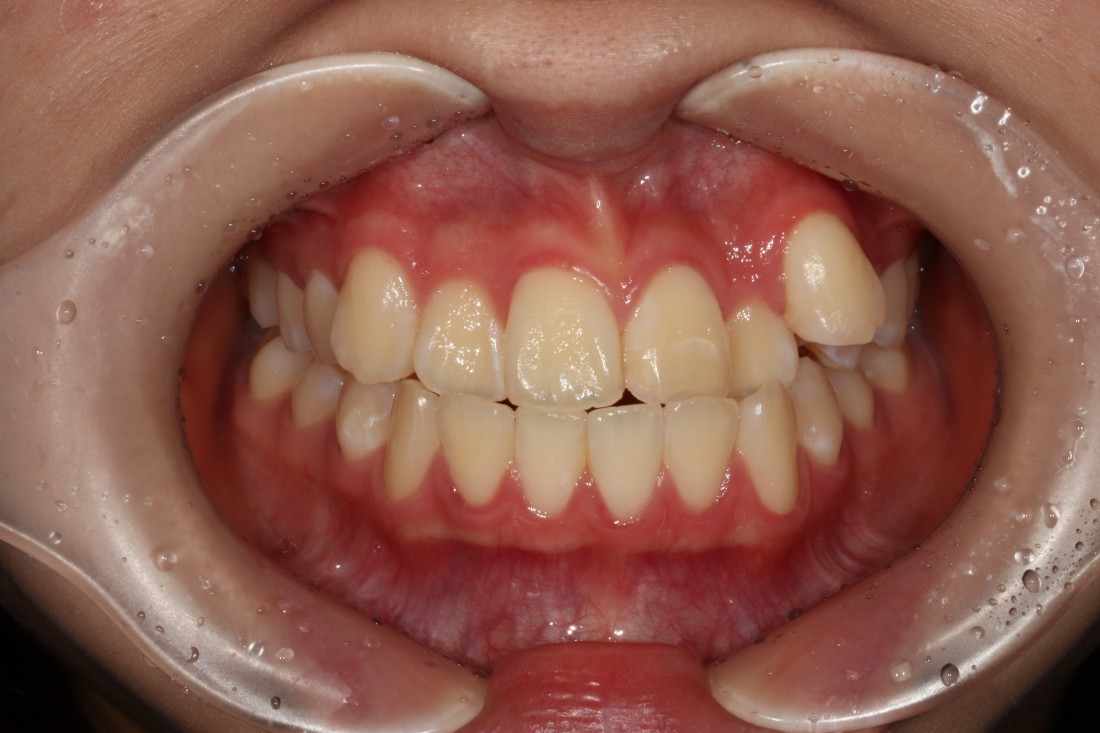

수완동 교정치과,

교정전문의 대표원장 진료

확인하셨나요?

수완동 교정치과를 선택할 때는

경험많은 교정전문의 대표원장이

세밀한 상담부터 치료계획,

월 정기진료 및 교정 후 관리까지

꼼꼼하게 책임지고 관리하는

교정치과인지 확인하는 것이

가장 중요합니다.